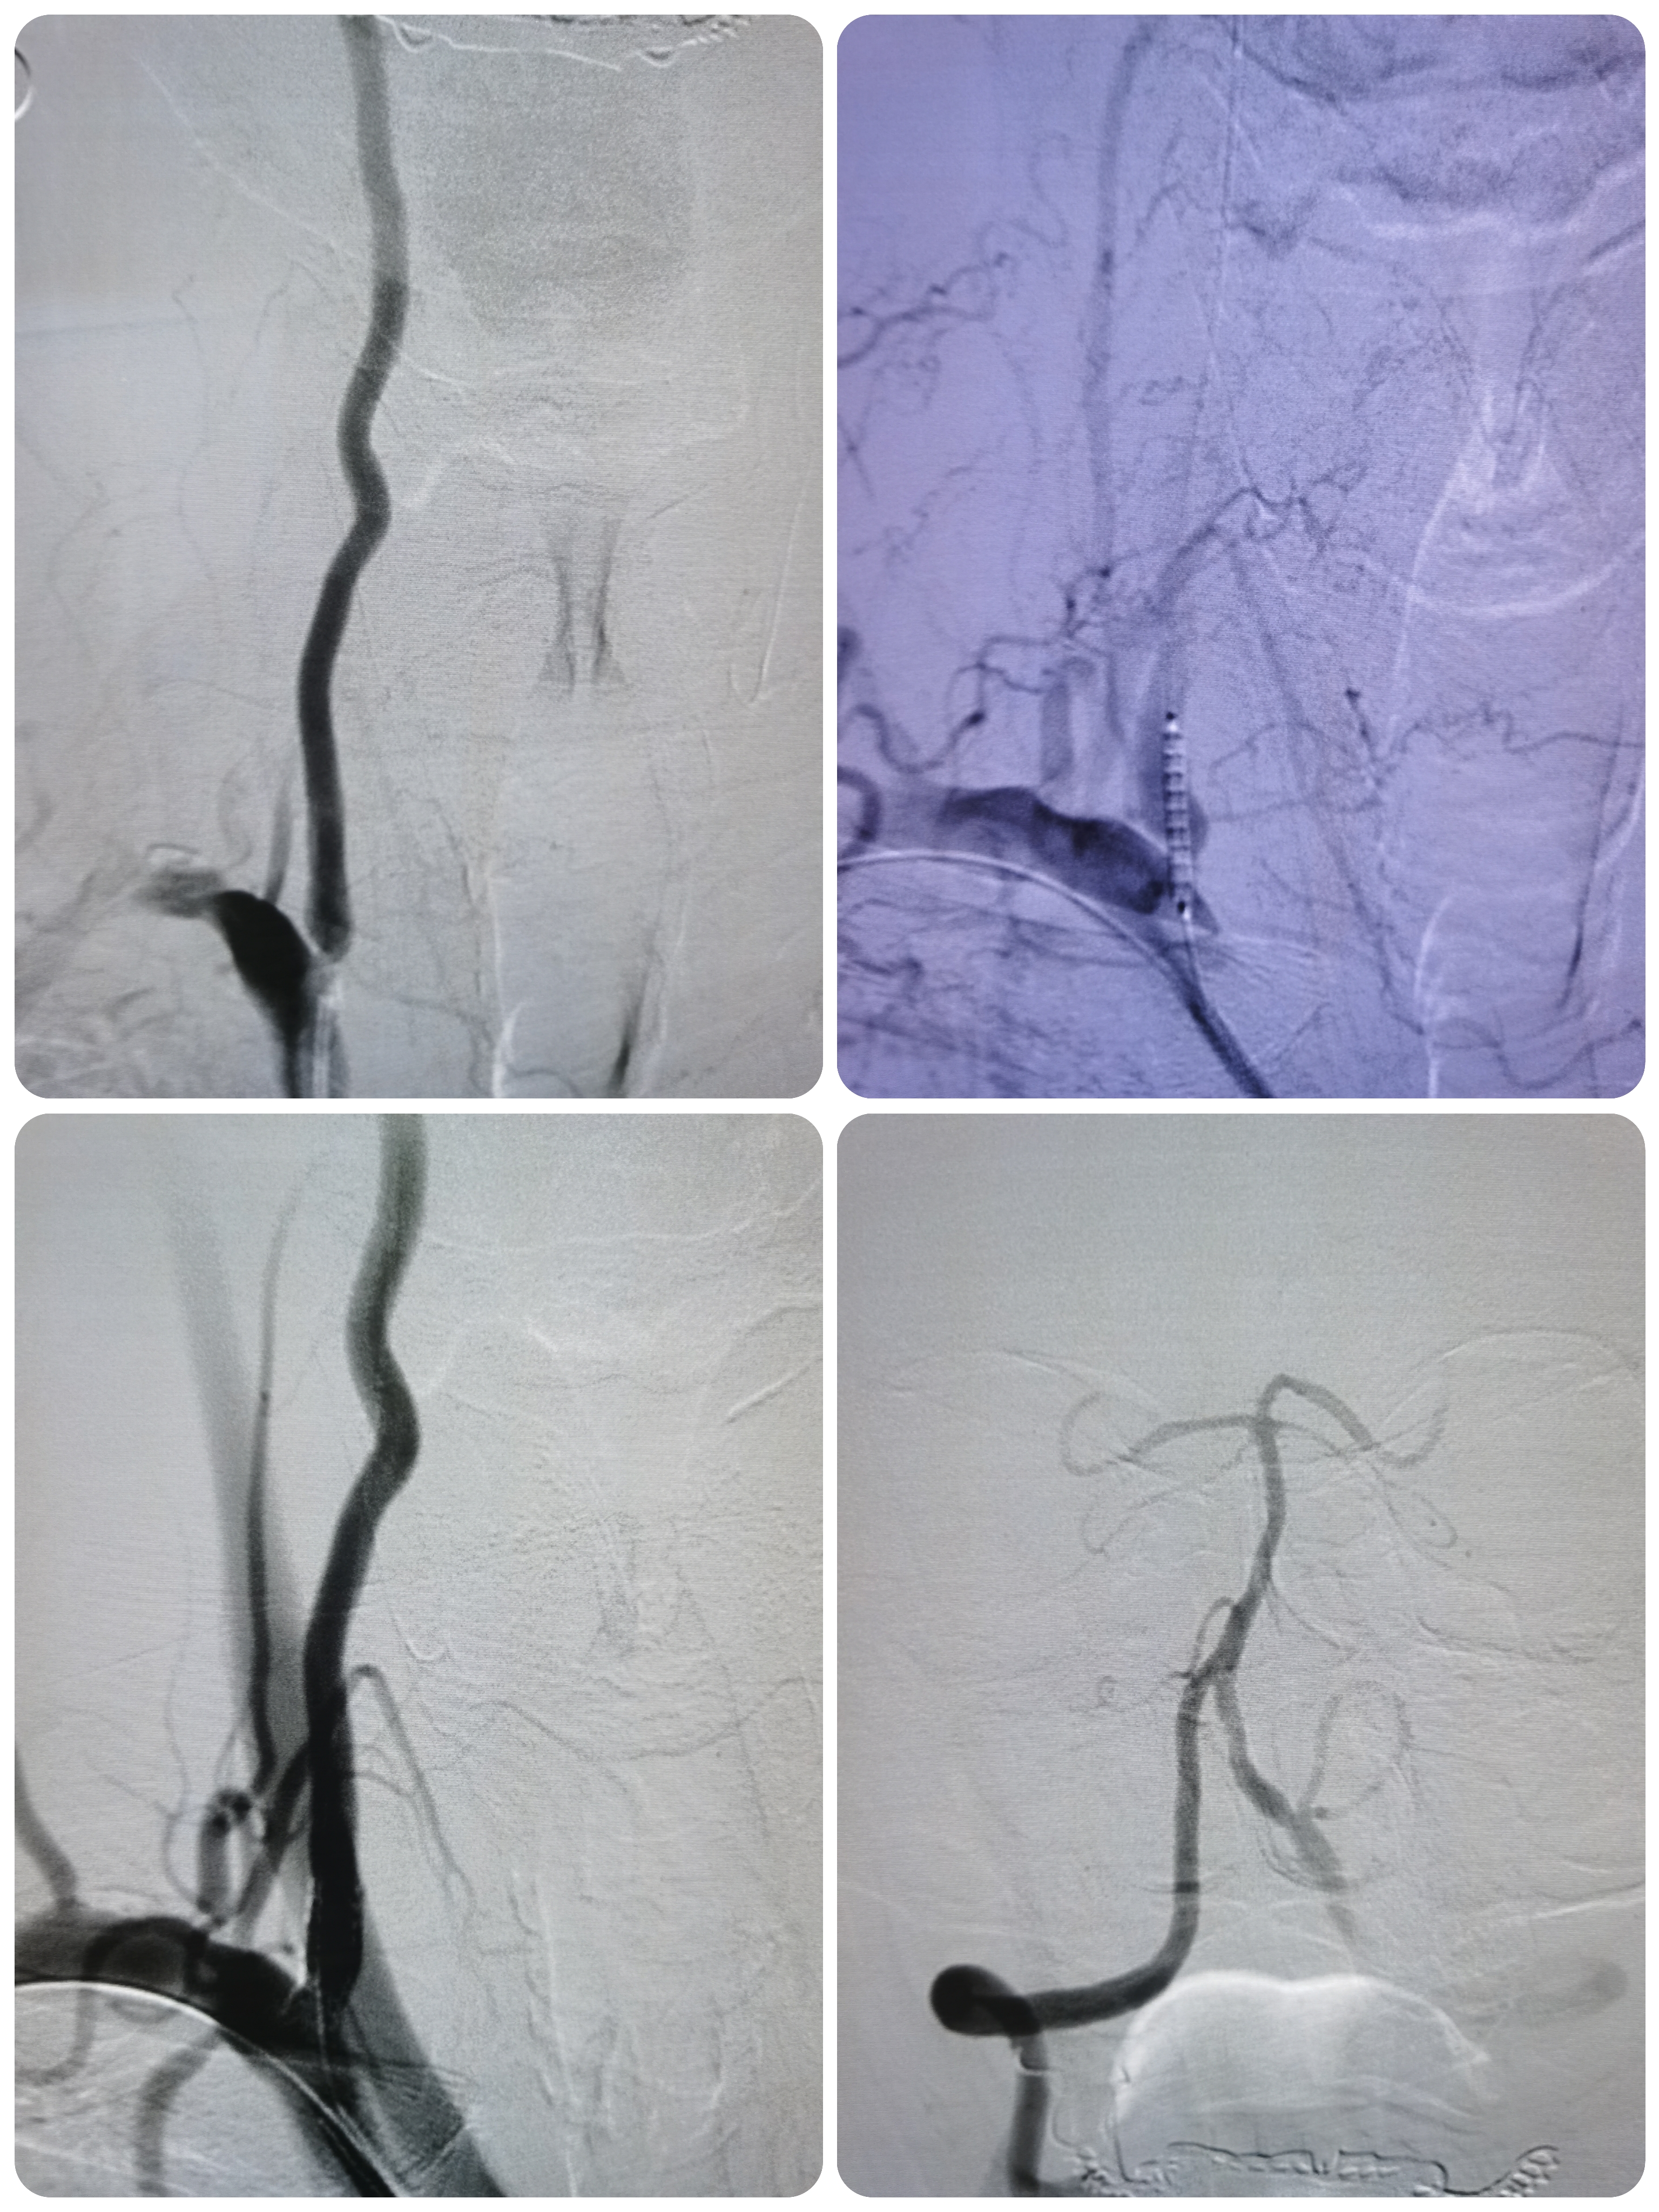

DSA示右椎动脉优势,起始部极重度狭窄,左侧椎动脉完全反向血流,动脉晚期可见左侧锁骨下动脉闭塞端。

右椎动脉起始部极重度狭窄。

右颈内动脉窦部重度狭窄,局部斑块不稳定。

左侧锁骨下动脉起始部完全闭塞。

1、造影明确左侧锁骨下动脉起始部完全闭塞,右椎造影可见左椎返流,晚期可见圆钝的锁骨下动脉闭塞端,结合病史考虑闭塞时间较长。

2、右椎动脉起始部极重度狭窄,系责任血管。

3、右侧颈内动脉起始部重度狭窄,局部斑块不稳定,且右侧后交通动脉开放。